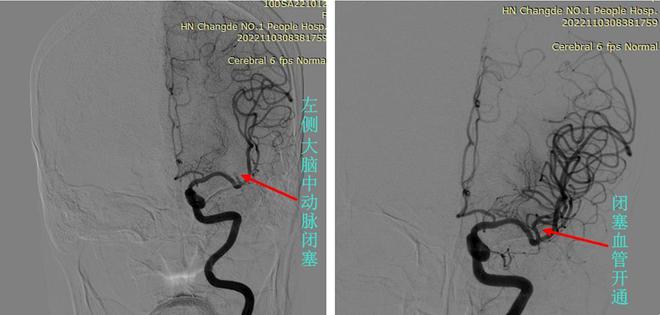

图左:11月3日,术中脑血管造影显示,静脉溶栓治疗后,张奶奶的左侧大脑中动脉仍然闭塞;图右:左侧大脑中动脉取栓术后,闭塞血管开通